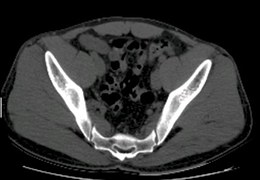

ANYTHINK 经导管主动脉瓣膜置换术分析系统